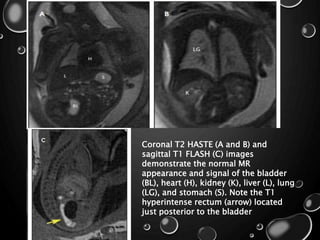

Coronal T2 HASTE (A and B) and

sagittal T1 FLASH (C) images

demonstrate the normal MR

appearance and signal of the bladder

(BL), heart (H), kidney (K), liver (L), lung

(LG), and stomach (S). Note the T1

hyperintense rectum (arrow) located

just posterior to the bladder

Coronal T2 HASTE(A and B) and sagittal T1 FLASH (C) images demonstrate the normal MR appearance and signal of the bladder (BL), heart (H), kidney (K), liver (L), lung (LG), and stomach (S). Note the T1 hyperintense rectum (arrow) located just posterior to the bladder